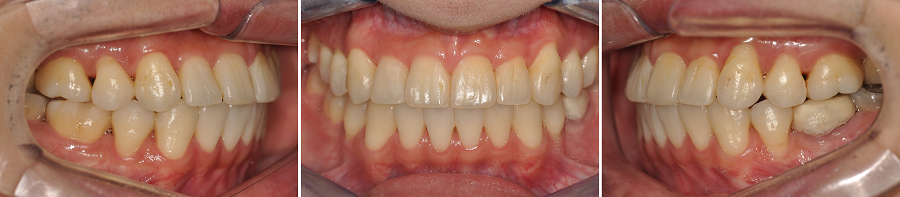

이번 환자분은 처음 내원하셨을 때부터 여러 치아 문제들이 동시에 존재하는 케이스였습니다.

단순 배열 문제가 아니라, 치아 결손·치아 경사·대구치 전방이동· 송곳니 덧니·치아 파절·충치 다수·심미적 문제가 한꺼번에 얽혀 있었죠.

✔ 초진 특징 요약

• 골격성 2급 부정교합

• 상악 우측 제2소구치 : 신경치료 후 크라운 수복을 미루다가 치아 파절

• 상악 좌측 제2소구치 결손 → 좌측 상악 대구치들의 전방이동

• 상악 양측 견치 공간 부족 → 높은 위치(High Canine)

• 하악 제2소구치 양측 모두 심한 설측경사

→ 그 공간으로 제1대구치가 전방 쓰러져 제2소구치의 공간이 거의 없는 상태

• 구강 내 충치 및 수복 필요 치아 다수

• 상악 전치부 순면 변연융선이 과도하게 발달 → 심미적 문제 + 브라켓 부착 어려움

치료 결과 — 교합과 배열이 동시에 개선됨

높은 위치에 있던 상악 양측 견치가 제자리로 배열

✔ 상악 우측 제2소구치 발치공간 폐쇄와 상악 좌측 구치 후방이동을 통한 구치 관계 안정화

전반적인 치열의 흐름이 정상궤도로 회복되었습니다.

환자분의 일정에 맞추어 치료를 종료하다보니, 정중선을 완벽히 맞추지 못한 점이 아쉽습니다.